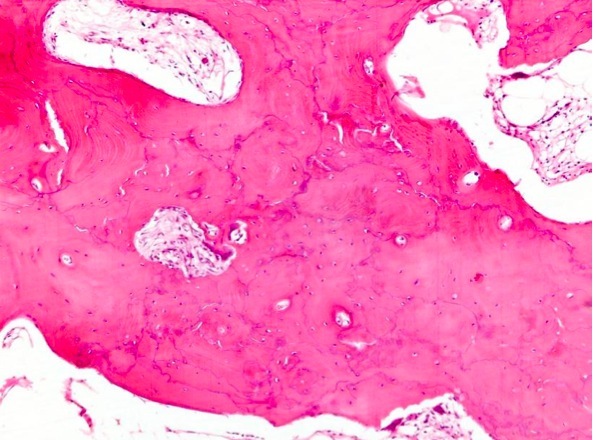

Paget’s Disease: Metabolic Bone Disease -> Abnormal bone modeling/remodeling

X-Ray

Gross:

Microscopic:

Etiology

Pathogenesis

Sx: often Asx and incidental finding

Diagnosis:

C&C: